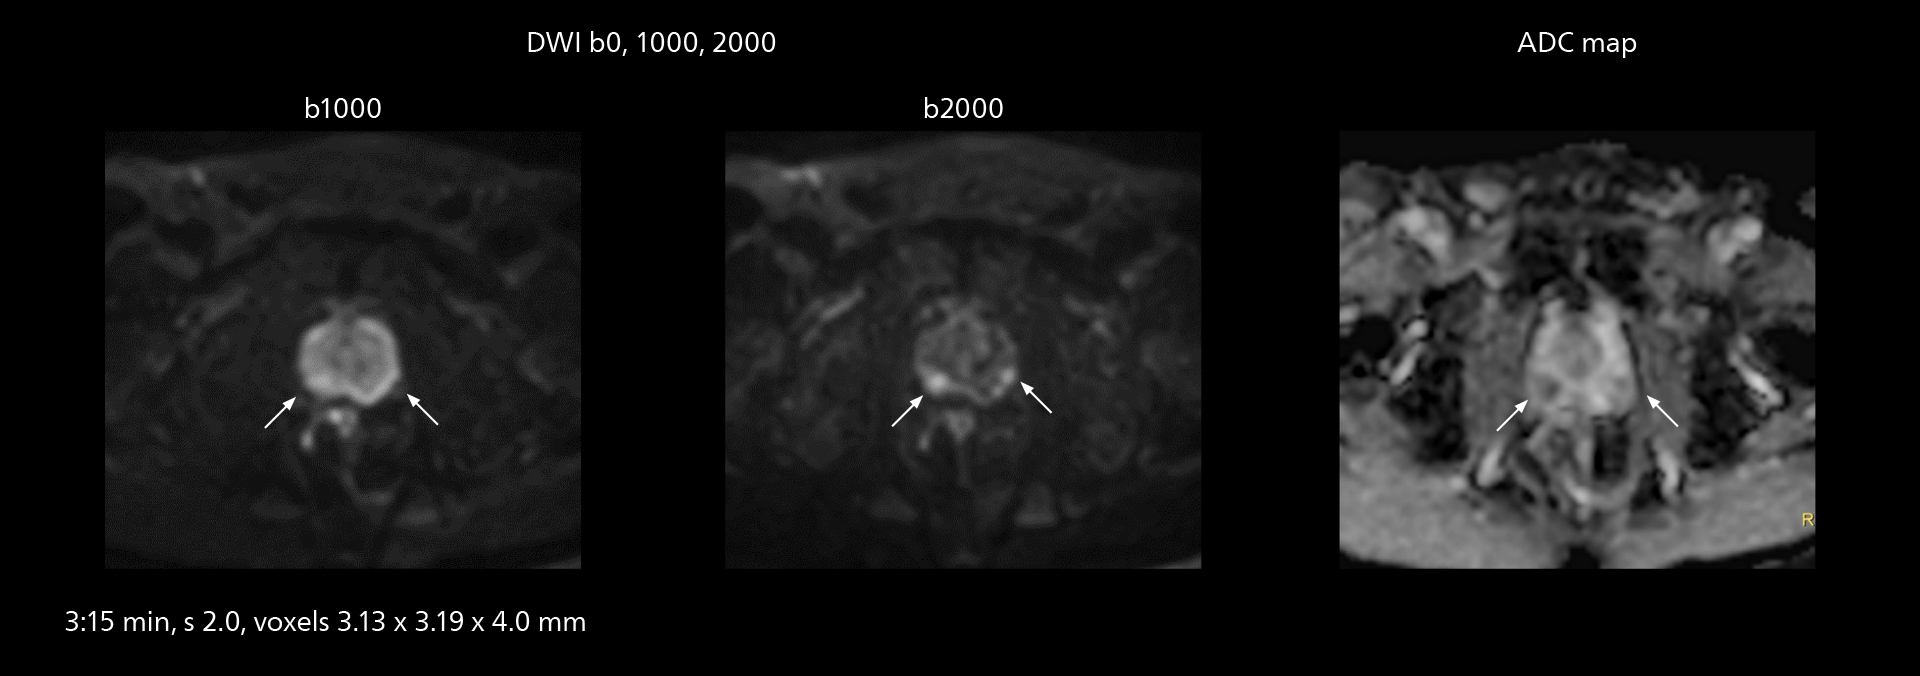

Diffusion studies benefit from powerful gradients

The high performance of the Vega HP gradients is particularly impressive in DWI. “The Vega HP gradients enable us to scan faster and use b-values as high as 2000, for example in prostate DWI and in DWIBS, which provides image quality that is remarkably improved over the previous system and we are able to more easily see lesions.”

MRI of prostate

Examples of prostate imaging showing faster scan times and improved resolution illustrate the power of SmartPath to Elition X in this case of prostate cancer with PI-RADS score 4.